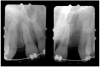

Periapical radiographs were taken to help determine the mesial-distal inclinations of the adjacent tooth roots (Figure 1). The radiographs revealed a serious issue, convergent roots for the right canine and right central, which eliminated that area as a potential implant-receptor site. The space between the left central and canine teeth was minimal, although the roots were relatively parallel. Clinical examination (manual palpation of the root eminences superiorly to the vestibule on the right side) confirmed the root convergence (Figure 2A). The flat, wide zone of the keratinized tissue and lack of interdental papilla was evident for the missing right lateral incisor. There was a marked difference in clinical appearance for the left lateral, which could impact the eventual plan of treatment (Figure 2B). Other significant clinical findings included bilateral facial bone concavities, which existed as a result of the congenitally missing tooth roots. As a diagnostic cue to the underlying bone topography, it is important to follow the demarcation between attached and unattached gingival tissue, and note the crestal width of the available keratinized tissue (Figure 2C).

Figure 1  Pretreatment radiographs revealed convergent roots for the right canine and right central.

Figure 1